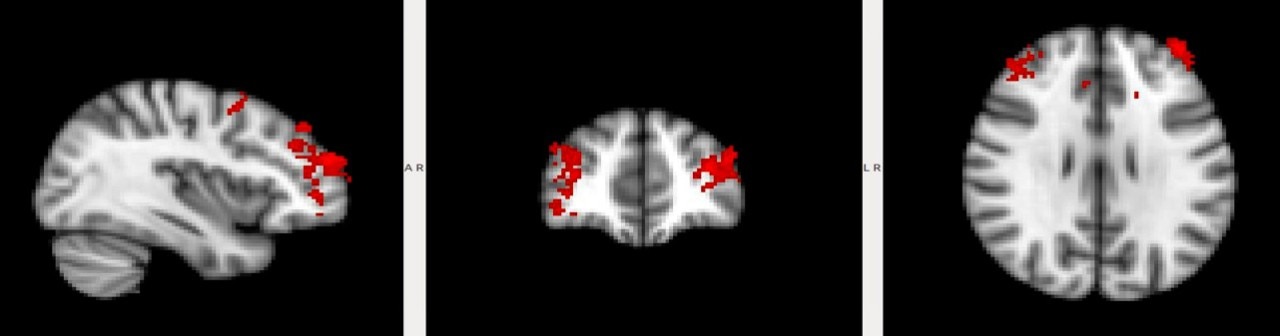

This procedure was used in human volunteers to find out what they find beautiful or ugly, focusing on the three main design choices. Merel Bekking, together with Dr. Scholte, developed a set of stimuli of 252 images. Subjects were put in an MRI scanner for an hour and where shown 5 different types of textures (wood, paper, plastic, steel, stone), 10 different colors, 8 different shapes (round, organic, square, rectangular, presented open or closed), and four types of paintings (violent, erotic, social activity’s, food).

Brain activity was mapped for a group of 20 individuals by the Spinoza Center. The people participating in the study were between the age of 20 and 30, all received a higher education degree or are in the process of receiving one. After the subjects were scanned the results were analyzed for the three design choices separately. Using different scientific models Dr. Scholte was able to create a list of likes and dislikes for these three main design choices.